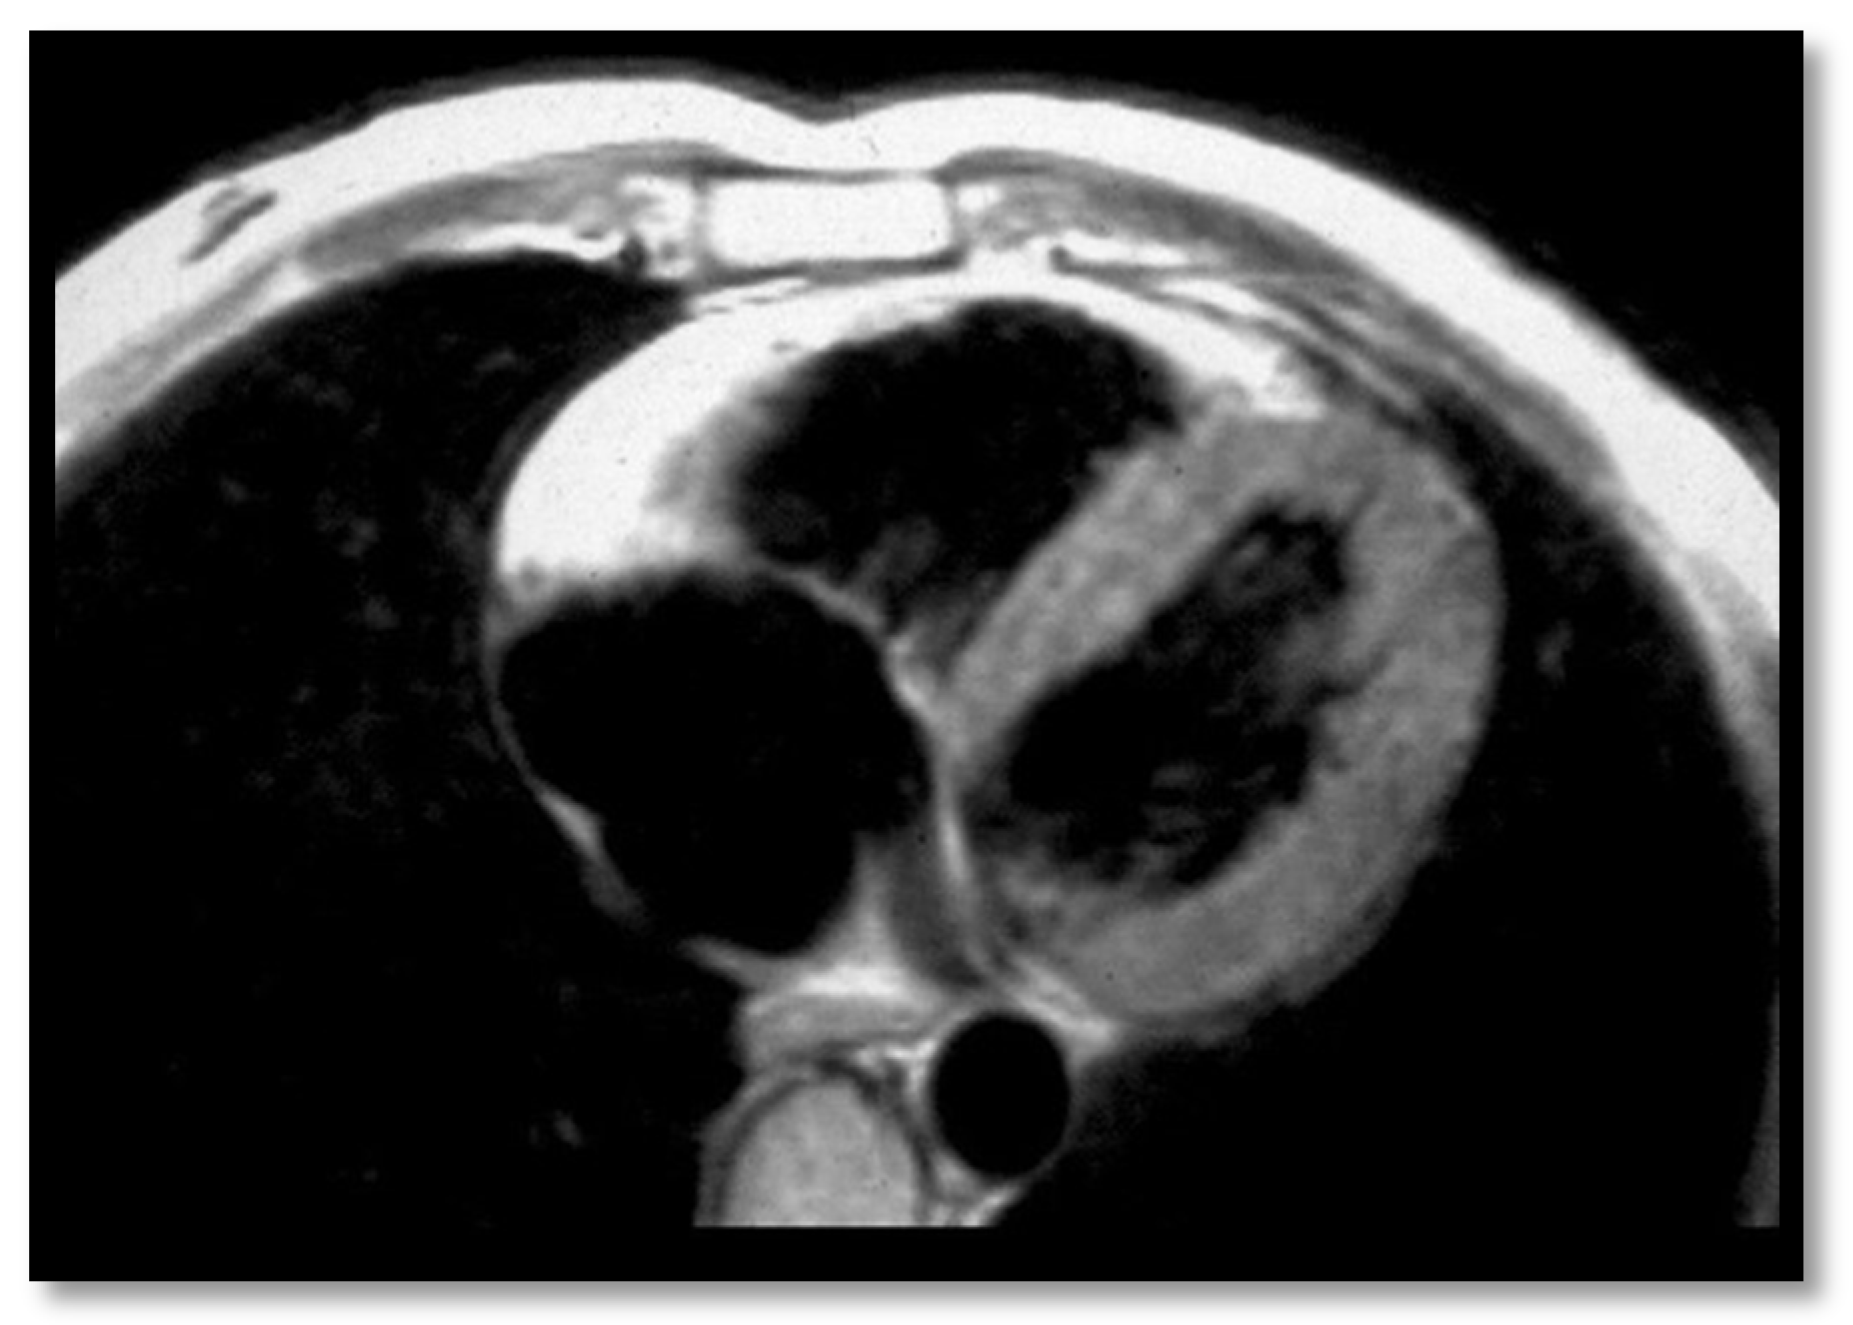

- RV contraction disorders and functional abnormalitiesUnlike the initial diagnostic criteria, the 2010 Revised Task Force Criteria [12] are quantitative rather than qualitative. Three types of changes were included: (1) segmental RV contraction abnormalities, (2) dilation of the RV, and (3) reduction of the RV ejection fraction. It is notable that intramyocardial fat or delayed enhancement are not included in the criteria for differential diagnosis strictly because these changes can be found in healthy people or in other diseases affecting the right ventricle. The association between akinesia/dyskinesia or RV regional contraction asynchrony with RV volume dilation or RV ejection fraction <40% is considered a major criterion for the diagnosis. As mentioned beforehand, the Revised Criteria are quantitative. Therefore, RV dilation is defined as the ratio of RV volume/body surface area > 110 mL/sqm in men or >100 mL/sqm in women. The minor criterion is defined as the presence of akinesia/dyskinesia with decreased ejection fraction of 40 to 45%, contraction abnormalities, or increased RV volume between 100 and 110 mL/sqm in men or 90 and 100 mL/sqm in women. It is worth noting that microaneurysms as well as segmental RV dilatations were removed from the Diagnostic Criteria because they are rather subjective and challenging to evaluate.

- Decrease of the RV ejection fraction(EF) is a diagnostic key element and occurs when several areas of impaired contraction cumulate and impair the general contractility function or when the dilated right ventricle. Taking into consideration the degree of EF decrease <40% or between 41% and 45% is rather important, as this criterion, together with the contraction abnormalities, may represent either a minor or major diagnostic criterion for ARVC [12,45].

- RV dilation is also a key element for the diagnosis of ARVC. It can be segmental or global. Segmental expansion can affect only the RVOT or parts of the RV such as the basal free wall or the middle third of the free wall. It is a diagnostic criterion with high sensitivity and specificity for ARVC (Figure 3). Only the global dilation of RV is considered a diagnostic criterion for ARVC because segmental dilatation is rather difficult to interpret [12,45].